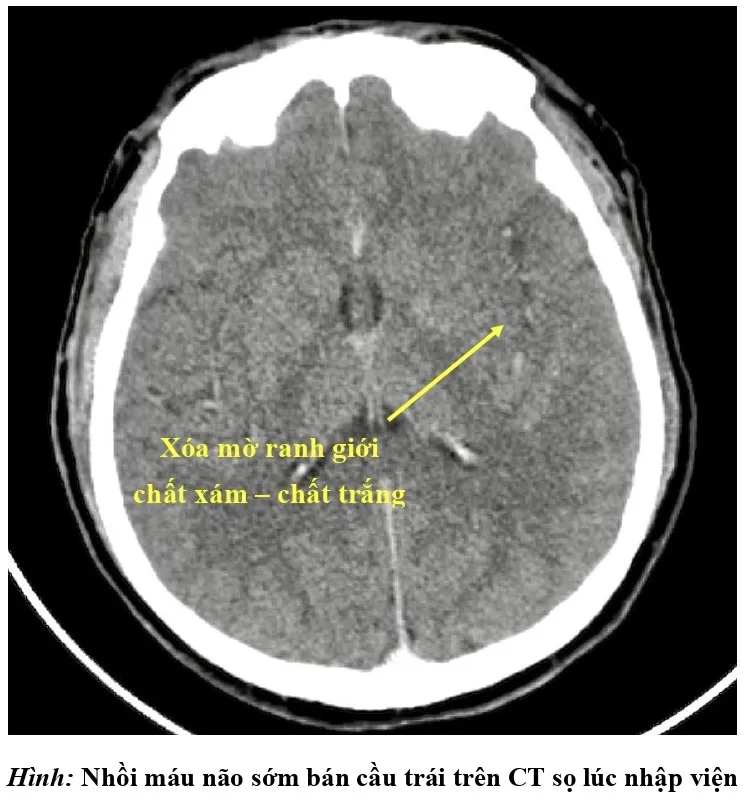

Bác sĩ chẩn đoán bệnh nhân bị đột quỵ nhồi máu não bán cầu trái giờ thứ 2 do tắc động mạch cảnh trong trái và động mạch não giữa trái bởi huyết khối.

đột quỵ nguy kịch - 1

Kết quả chụp CT lúc nhập viện của bệnh nhân đột quỵ nguy kịch. Ảnh: BVCC